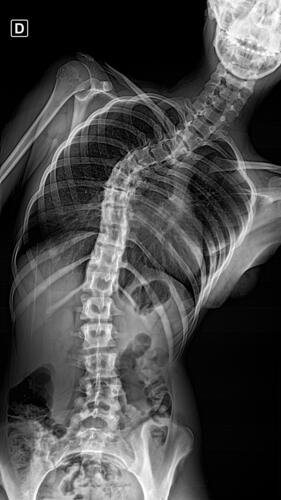

A Vá tem 13 anos e precisa urgentemente realizar uma cirurgia na coluna.Valentina foi surpreendida com o diagnóstico de escoliose hepática grave com 67 graus de desvio (desvio longitudinal da coluna), e precisa realizar com urgência a cirurgia corretiva, os exames foram realizados em Porto Alegre, mas a cirurgia está marcada para dia 13/07 em São Paulo devido a gravidade do caso, para isso a família terá que ficar residindo próximo ao hospital em São Paulo por no mínimo 30 dias para uma plena recuperação. Sabemos bem que qualquer procedimento cirúrgico é delicado, na coluna então nem se fala.Após o diagnóstico e o prognostico dessa doença a família se desfez de alguns bens (carro e moto) para cumprir os prazos dos exames e consultas, necessitando agora arrecadar o valor para a estadia da pequena Valentina e seu pós operatório (medicação, consultas e fisioterapia).

Em anexo os exames (laudo e imagens) para expressas a gravidade do caso.